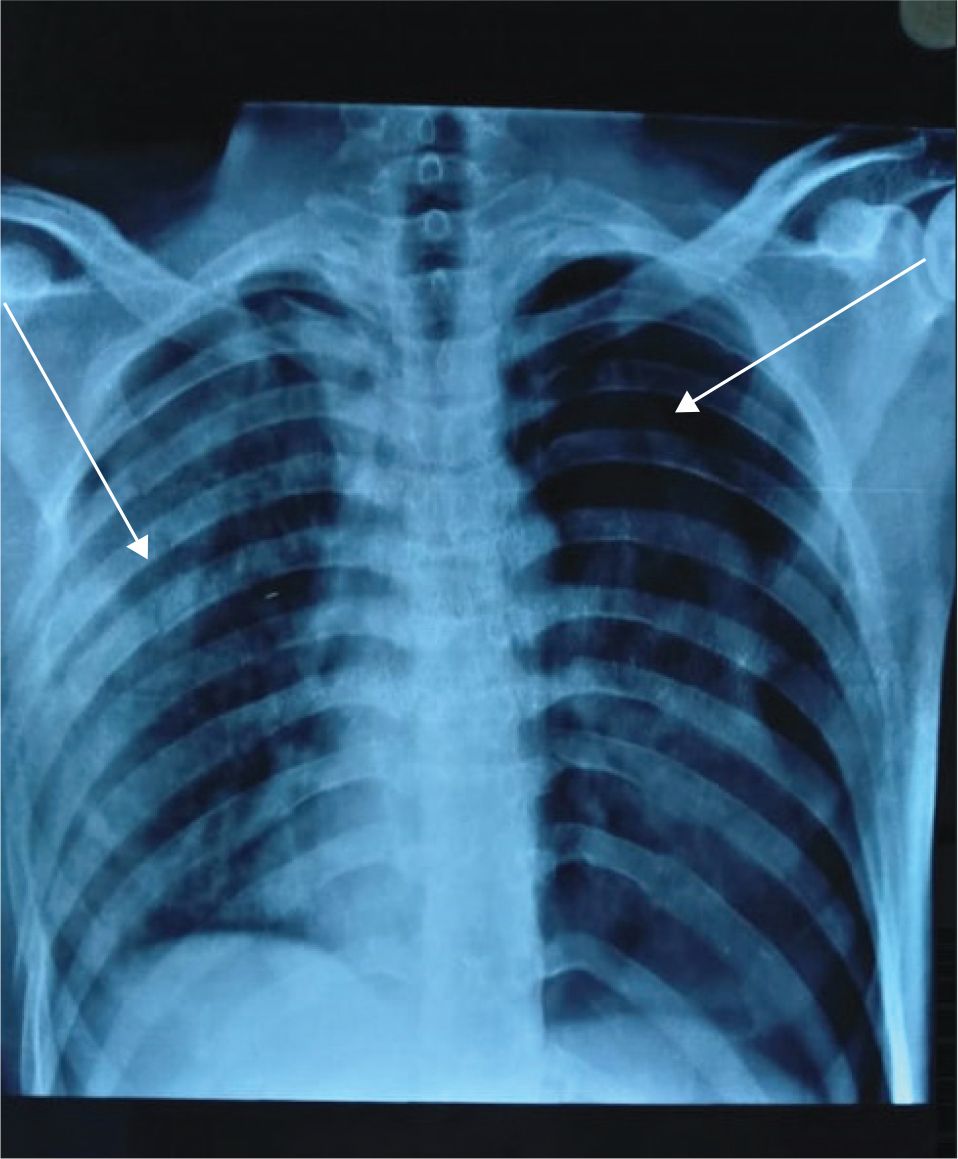

Chest X-ray (Figure 3) revealed bilateral pneumothorax primarily on the left, with a mediastinal shift towards the right side. A fracture of the right second and third ribs and a segmental fracture of the right 4th to 8th ribs were suggestive of a flail chest. Gross pneumothorax of the left lung resulted in a partial collapse of the left lung. High-resolution computed tomography (HRCT) of the chest revealed extensive right and minor left pneumothorax, bilateral lung contusions, a right clavicle medial end fracture, and multiple rib fractures.

Fig 3

Fig. 3. Chest X-ray of the patient revealed pneumothorax (right arrow) and rib fractures (left arrow).